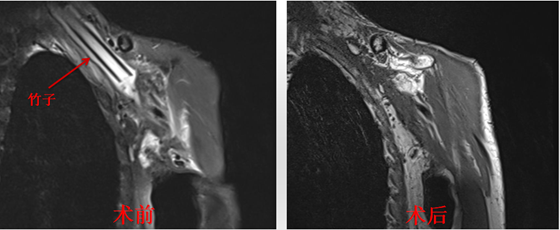

在反复仔细询问患者受伤及后续治疗病史后,完善相关检查,对病情进行全面评估后,确定从腋窝插入的“竹子”深入颈胸部,位于锁骨下方,锁骨下动脉及肺尖旁。根据患者实际情况,由整形美容烧伤皮肤科李连楚主任医师主刀,在全麻下为患者行左颈胸部清创探查异物取出术。全麻插管后,沿左腋部窦道口至颈胸部竹子插入方向进行切开,仔细探查,避开锁骨下动脉及周边神经,发现“竹子”,成功予以取出,异物为新鲜竹子断端,末端齐整,直径约1厘米,长约8厘米,再次仔细探查确定无残余异物后,反复清洗伤口窦道,放置引流管,予以修复封闭伤口,历时3个小时,完全取出“罪魁祸首”。术后安返病房,在医护团队精心治疗下,最终康复出院。